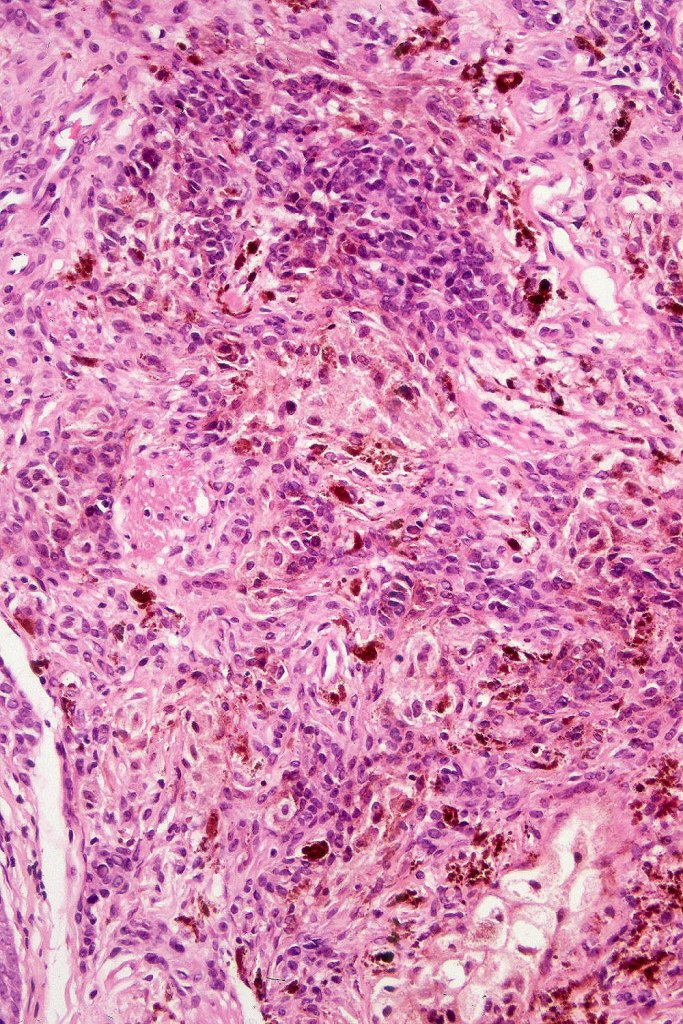

Combined Spitz & common blue nevus